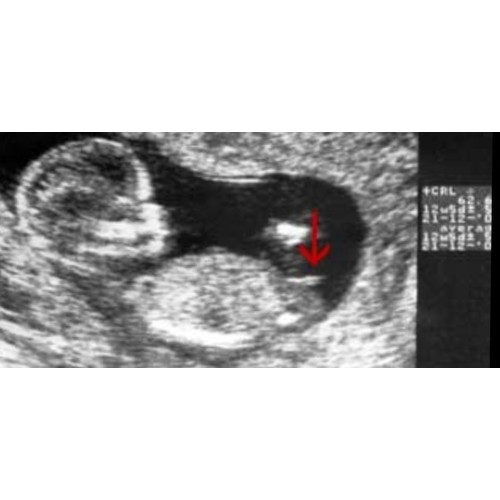

Is dat niet de navelstreng?? Althans dat zei mijn v.k. of. ?

Afgaand op de NUB theorie is mijne een meisje denk ik?